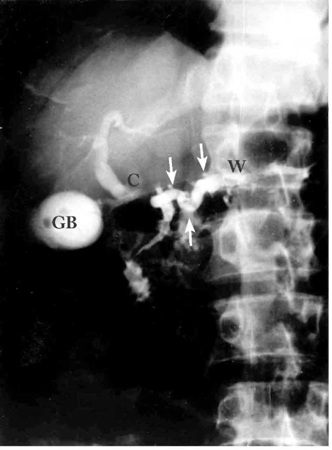

- ב-ERCP (Endoscopic retrograde cholangiopancreatography) אפשר להדגים פתולוגיות אחדות. אפשר להבחין כי צינור הלבלב כולל היצרויות והתרחבויות לסירוגין (תצלום 7.9), ואפשר להדגים אבנים בתוך צינור הלבלב (תצלומים 8.9 ו-9.9).